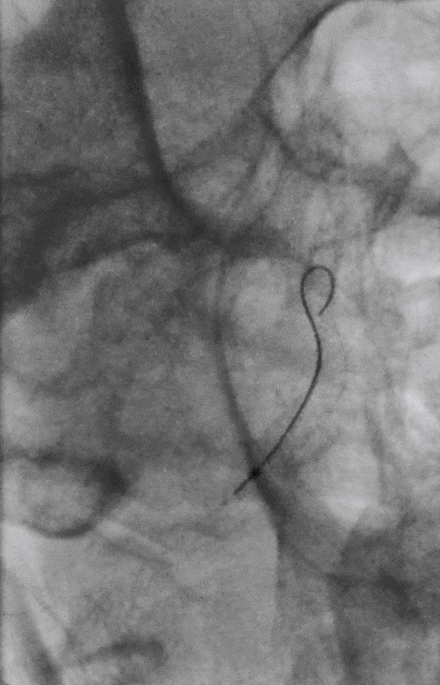

通桥白驹®球囊(2.5*10),先远后近扩张。

球扩后,狭窄改善。

Marksman到位。